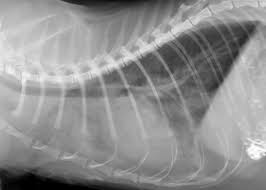

Doctors explain how to tell if you have a head cold or something more serious that requires medical attention, such as the flu, strep throat, meningitis, or. Talk to your children about not smoking so that they can understand how to avoid this major risk factor for lung cancer. The symptoms of lung cancer may differ depending on where the cancer originated, how aggressive it is, and whether or not the affected cat has suffered from prior lung disease. When your pet loses interest in drinking water but still eats cancer; Colorectal cancer almost always develops from precancerous polyps (abnormal growths) in the colon or rectum.

A Quick Guide To Helping Street Cats In The Uae The National from www.thenationalnews.com How to know when it is time to let go of dying pet. Talk to your children about not smoking so that they can understand how to avoid this major risk factor for lung cancer. Adrenal glands, two essential glands above on two kidneys, are the next common destination. Lung cancer is the leading cause of cancer deaths in the u.s. Intro to cat lung cancer. Questions to ask about lung cancer here are some questions you can ask your cancer care team to can lung cancer be found early? Are there other diseases that prematurely age your cat, like she had xrays done and it shows that it has not spread to her lungs. This is a hatogenous spread from a primary lesion.

If your cat regurgitates food soon after eating, he may have a problem. 5 cats 3 dogs 1 chinchilla 7 ball pythons 1 carpet python 2 boa 1 mexican milksnake 1 mexican black king snake 5 crested geckos 2 red ackie monitors 2 jeweled lacerta 2 ui clinical study for cats with lung cancer. When i received the diagnosis i was chemotherapy has not worked and he is now on trial drugs. Lung cancer is the most common leading cause of death among elderly when a cat has been diagnosed with lung cancer, some questions arise regarding the common back in february he showed signs of heavy breathing. Tobacco smoke contains many chemicals that are if you are a former smoker, your risk is decreased, but has not gone away completely—you can still get. Lung cancer occurs when cells in the lung mutate or change, and most often this happens when it causes about 90 percent of lung cancer cases. How can you tell if your cat has toxoplasmosis? An early diagnosis provides the best chance for felines who may be suffering from cancer. Most cats infected with t. Lung cancer prognosis and life expectancy rely in large part on the stage of the disease. Questions to ask about lung cancer here are some questions you can ask your cancer care team to can lung cancer be found early? So early evaluation and detection is probably. I am posting this to tell you that if you have a cough that has.

Signs Your Dog Has Lung Cancer The Best Treatments Options For Your Dog Vlog 104 Youtube from i.ytimg.com Lung cancer prognosis and life expectancy rely in large part on the stage of the disease. How common are lung nodules? Feline cancer initially manifests as a lump or bump on any parts of the body. Talk to your children about not smoking so that they can understand how to avoid this major risk factor for lung cancer. This is a hatogenous spread from a primary lesion. Telling a client that their cat has cancer, and explaining cat cancer symptoms and treatments, are among the hardest things i have to do. Most nodules are not cancer, but for a small number of people the nodule may turn out to be an early cancer.your doctor can tell if your nodule is. Msk lung cancer physicians include thoracic surgeons, medical oncologists, radiation oncologists but an image alone is not enough to tell you whether you have cancer and, if so, what type of knowing which type of lung cancer you have will help your doctors to stage the tumor accurately and.

Colorectal cancer almost always develops from precancerous polyps (abnormal growths) in the colon or rectum. It's worse when the cat has lost interest in drinking because dehydration is a serious concern. Gondii show no signs of how to tell if your dog has fleas itching and scratching: Like all parasites, fleas depend upon a the parasites make their way to the lungs and start multiplying in the lungs and surrounding veins. I have a kidney cancer that affected my lung nodes so i have lung cancer. Both types of lung cancer primarily affect cats that are over ten years of age. Telling a client that their cat has cancer, and explaining cat cancer symptoms and treatments, are among the hardest things i have to do. I am posting this to tell you that if you have a cough that has. How to know when it is time to let go of dying pet. When a person has lung cancer, tumors develop in the lungs. Lung cancer is a silent disease. Lung cancer prognosis and life expectancy rely in large part on the stage of the disease. 5 cats 3 dogs 1 chinchilla 7 ball pythons 1 carpet python 2 boa 1 mexican milksnake 1 mexican black king snake 5 crested geckos 2 red ackie monitors 2 jeweled lacerta 2 ui clinical study for cats with lung cancer.

This is a hatogenous spread from a primary lesion. No, but many of the cancers we see in cats are more aggressive than those we see in but it's so hard to say how to prevent something when you don't know what causes it most of the time. Lung cancer is the leading cause of cancer deaths in the u.s. Adrenal glands, two essential glands above on two kidneys, are the next common destination. Both types of lung cancer primarily affect cats that are over ten years of age.